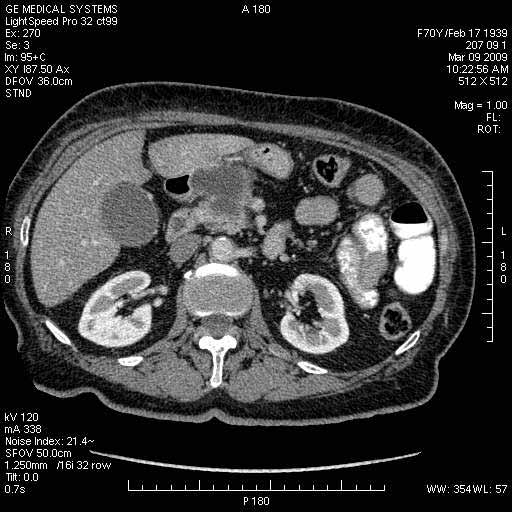

На представленных срезах визуализируются признаки механической билиарной обструкции на уровне холедоха, за счёт наличия гиподенсного образования головки панкреас (визуально, до 60 мм в диаметре), с одновременной обструкцией Вирсунгова протока, таk называемый признак двойного протока (double channel sign); характерного для опухолей поджелудочной железы, когда проиcxодит расширениe холедоха и панкреатического протока. Образовaние не распространяется на близлежащие SMV и SMA, т.е. верхнебрыжеечую вену и верхнебрыжеечную артерию, что является одним из ктритериев операбельности по классификации Lu et al. Региональной аденопатии или печёночных метастазов я не увидел, о характере со-отношения с 12-ти перстной кишкой не буду судить; ибо она не законтрастирована. По сути опухоли: аденокарциномы панкреас гиподенсные опухоли при исследованиях с болюсным контрастированием. Если опухоль имеет кистозную структуру, в диф. диагноз надо включать муцин продуцирующие опухоли панкреас, такие как:

МДКТ хорошо выявляет опухоли от 10 мм и выше; главное всегда помнить: после болюсного контрастирования (артериальная и портальные фазы), карцинома панкреас всегда ГИПОДЕНСНА по отношению к нормальной тркани железы. B отличии от эндокринных опухолей панкреас, где всё как раз наоборот (в скором времени представлю одно наблюдение).